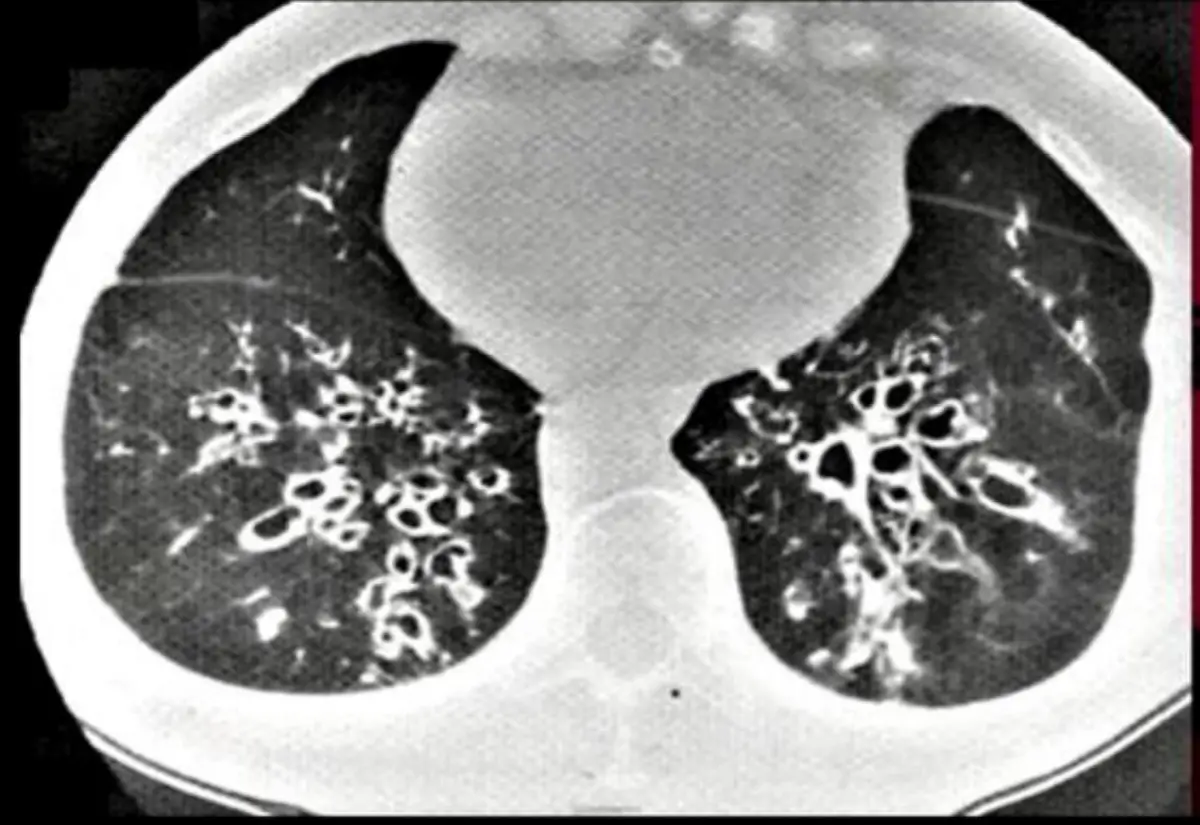

某60歲女性因慢性咳嗽與濃痰來內科門診。聽診時在雙側下肺葉有聽到crackles。胸部電腦斷層如圖。請 問下列診斷何者可能性最高?

CT影像顯示雙側下肺葉大量、異質性的支氣管擴張,包括:

- Varicose bronchiectasis:支氣管呈「串珠狀」不規則狹窄與擴張交錯(beaded appearance),壁厚不均(turn0search1)(ncbi.nlm.nih.gov)。

- Cystic bronchiectasis:末端支氣管擴張成薄壁囊腔叢集(cluster of cystic spaces),類似「葡萄串」外觀(turn0search1)(ncbi.nlm.nih.gov)。

- 支氣管壁增厚、管腔內可見分泌物阻塞(muc